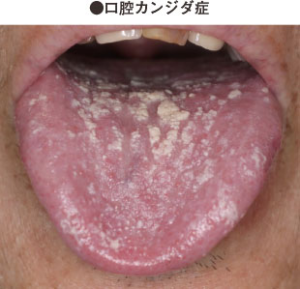

白斑を主とする病気

②口腔カンジダ症:口腔粘膜に小斑点状の偽膜を生じ、ぬぐい去る事ができる。